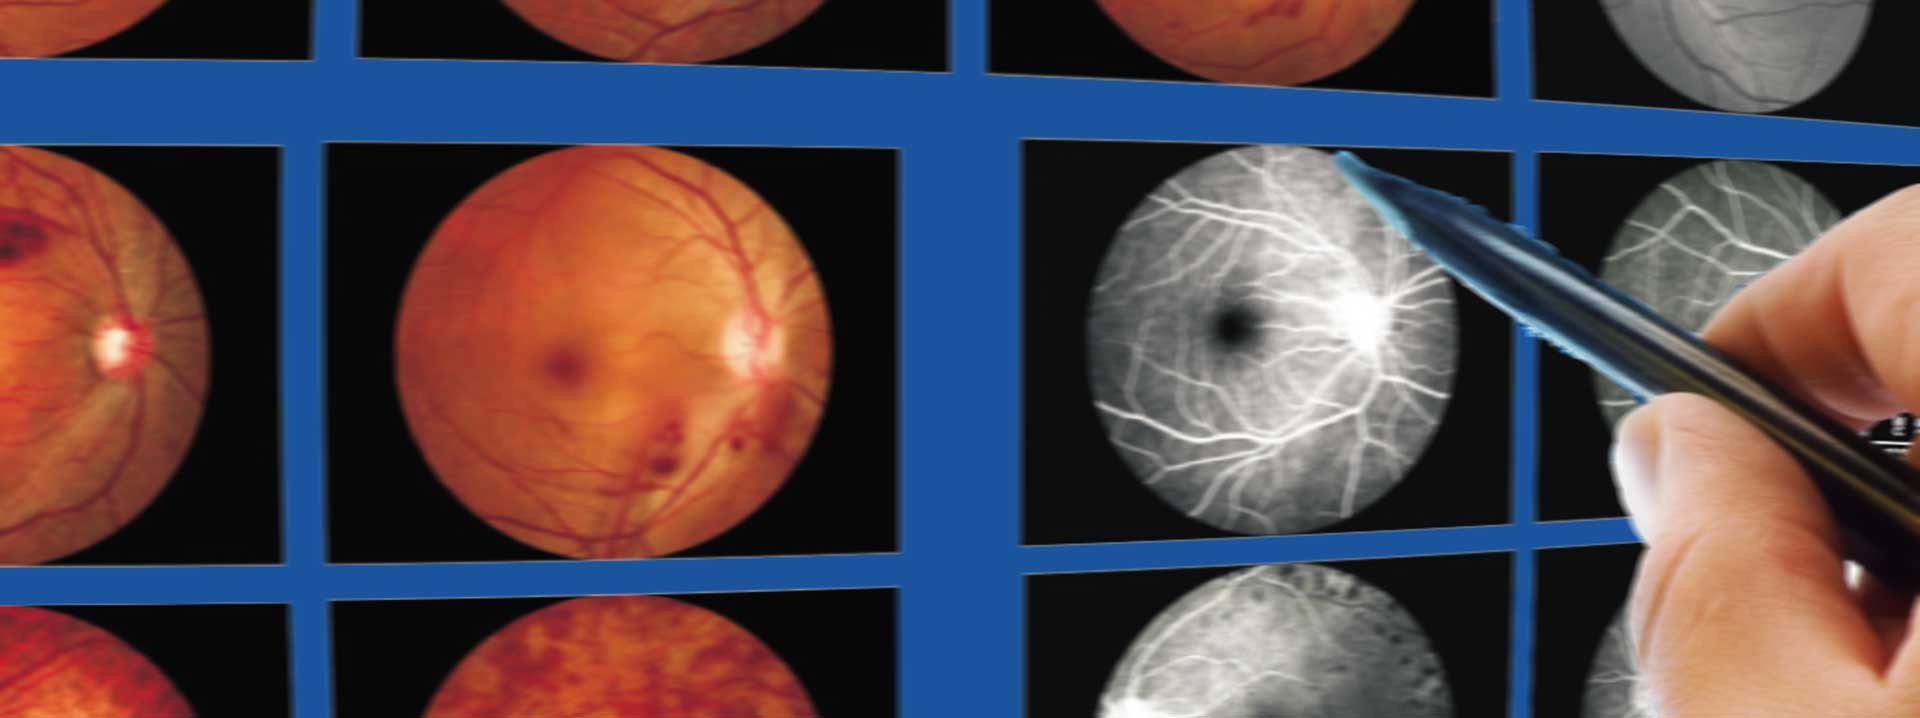

Diabetic Retinopathy

(fundus image)

- Automatic lesion detection

- Highlight lesion location

- Stage classification